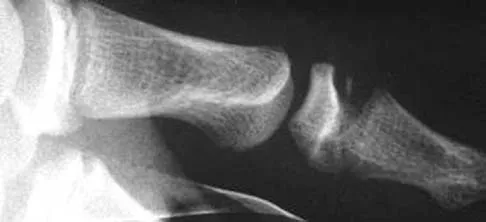

An active 47-year-old woman with rheumatoid arthritis reports forefoot pain and deformity and has difficulty with shoe wear. Examination reveals hallux valgus and claw toes. A radiograph is shown in Figure 10. What is the most appropriate surgical treatment?

Rheumatoid arthritis commonly affects the metatarsophalangeal joints, which become destabilized with time resulting in hallux valgus and dislocated lesser claw toes. The result is metatarsalgia as the dislocated claw toes "pull" the fat pad distally. Severe hallux valgus reduces first ray load, which compounds the metatarsalgia because the load is transferred to the lesser metatarsal heads. First metatarsophalangeal arthrodesis restores weight bearing medially and corrects the painful bunion. Metatarsal head resection slackens the toe tendons to allow correction of the claw toes by whatever means necessary and decreases plantar load over the forefoot. Rheumatoid arthritis in the first metatarsophalangeal joint will continue to progress if osteotomies or a Lapidus procedure are performed. Keller resection arthroplasty increases transfer metatarsalgia and reduces push-off power during gait. Flexor-to-extensor tendon transfer of the lesser toes does not address the metatarsalgia and does not correct the dislocation of the metatarsophalangeal joint. Coughlin MJ: Arthritides, in Coughlin MJ, Mann RA (eds): Surgery of the Foot and Ankle, ed 7. St Louis, MO, Mosby, 1999, p 572.